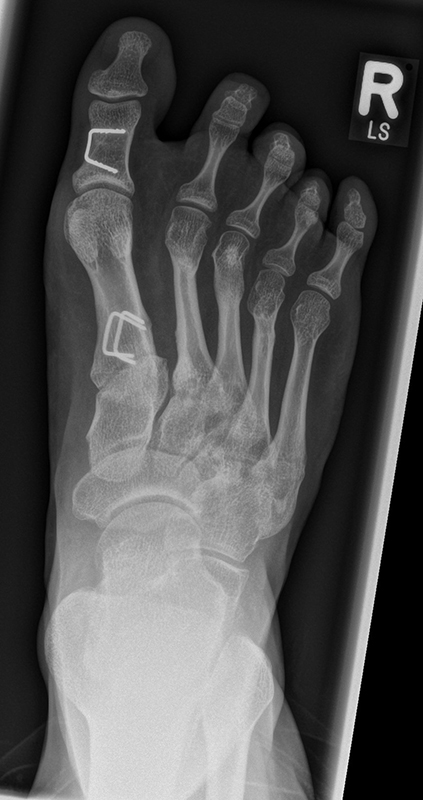

In der Regel bestehen aktive Wachstumsfugen bei Mädchen bis zum 12. und bei Jungen bis zum 14. Lebensjahr, mit Abweichungen von einem Jahr nach unten und nach oben. Präzise Informationen unter anderem darüber gibt das präoperative Röntgenbild (Abb. 2).

Abb. 2 a-c: offene Wachstumsfugen MT I Basis und Zehen (a), teilweise geöffnete Wachstumsfugen (b) und geschlossene Wachstumsfugen (c).

Zum Lesen der Bildbeschreibung und zur Vollansicht bitte die Bilder anklicken. Bilder: A. Helmers.